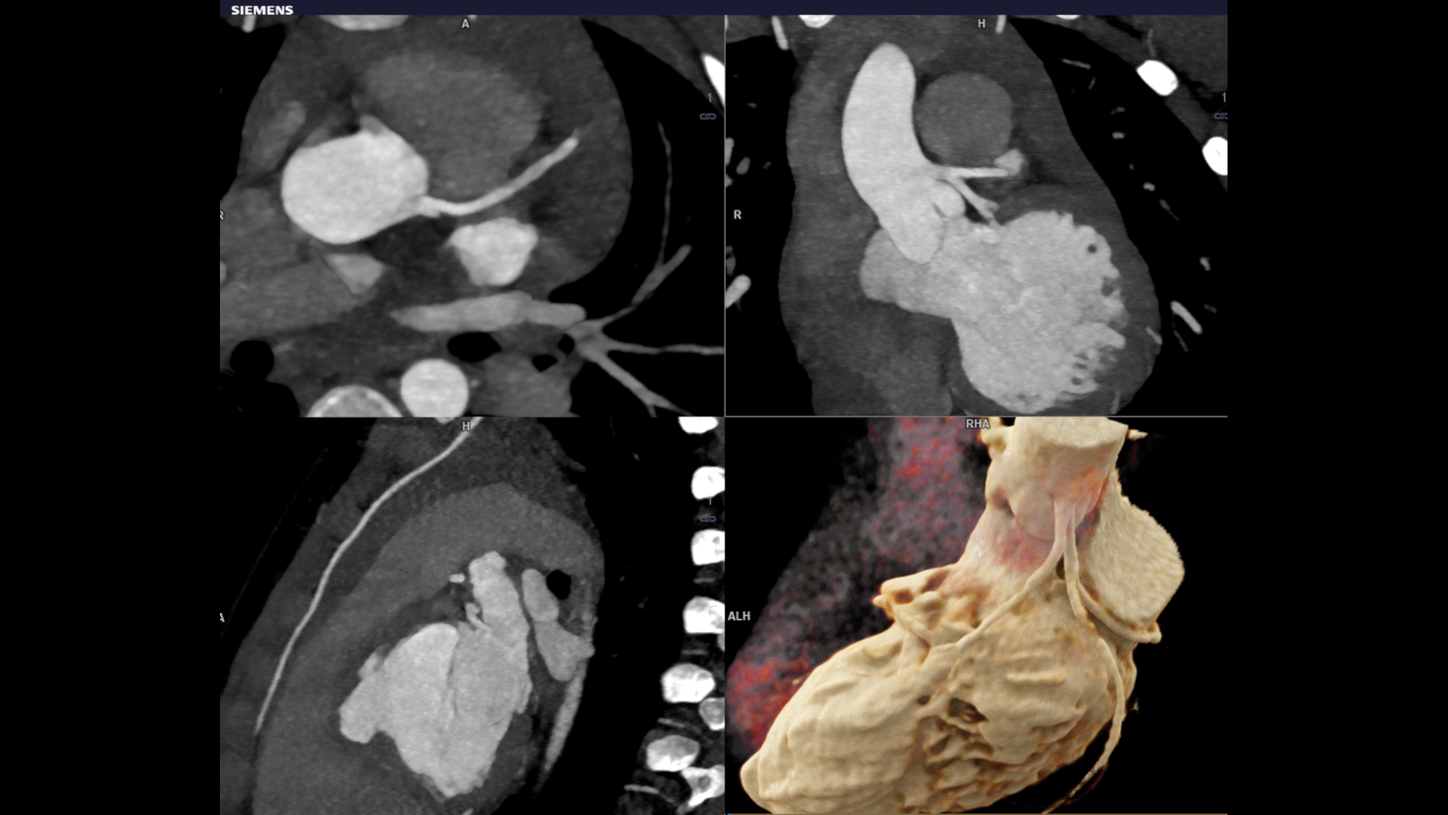

The objective of the whole technique is to get images from the scanning procedure to achieve sound diagnosis in child CHD. Evaluation involving complex anatomy of the body such as the heart, liver, spine & individual blood vessels. The cross sectional details in pediatric imaging are extremely small that demands for good quality imaging. At the same time, radiation dose in this category is a primary concern. Pediatric CT imaging means you have to keep the radiation doses at a bare minimum.

Dual source turbo flash spiral the combination of two sources, a high table feed (increasing scan speed up to 737 mm/s), rapid acquisition (0.25 s) and ultra-fast data transmission, and hence CT scanner makes its high temporal resolution (66 ms ). It enables extremely short scan times with very low radiation doses. Iterative reconstruction technique ADMIRE help to generate high quality images from low dose high noisy data set.

CHD is the most common congenital anomaly and causes more deaths in the first year of life than any other birth defect. Most cases of CHD require surgery or interventional procedures to restore the heart’s normal function. This recent technological improvement has been attributed to better imaging and improved understanding of the anatomy of CHD. Cardiac surgeons and radiologists collaborate in the treatment of children with Congenital Heart Disease (CHD). Faster imaging produces 3D reconstructions and models are to be used as planning tools for surgery. Turbo flash imaging is an excellent choice for the clinical evaluation of CHD especially as the imaging needs to be performed in free breathing and without sedation. Iterative reconstruction technique helps to create quality images from low dose noisy data.